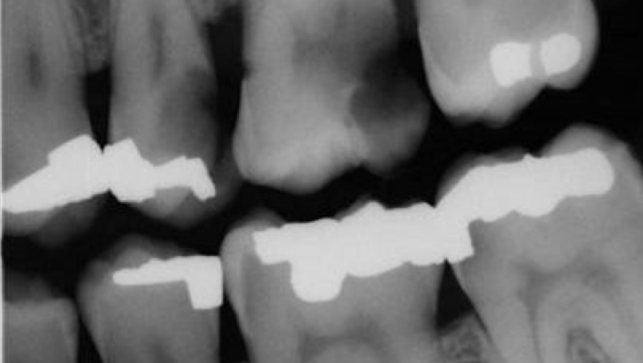

radiographic report

A old be 2 (as want to see mesial distal entirely)

37 - secondary caries mesial

36 mesial caries

Gross caries distal 25 and 26

Widening PDL 37

Bone loss upper left